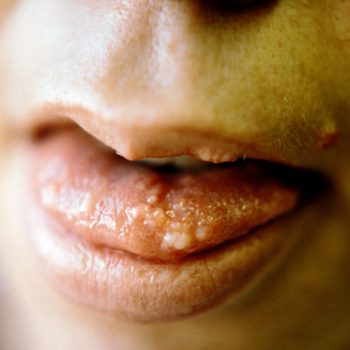

Sipple – Oral Mucosa Tumor (b)

Note what signs you see.

I (W. Wertelecki, M.D.) consider the mucosa signs typical of this syndrome also known as MEN (Multiple Endocrine Neoplasia) Type 2A, an autosomal dominant disorder. These tumors are known to be neuromas but also may be lipomas, angiofibromas, etc. For a perspective see this patient’s gallery.